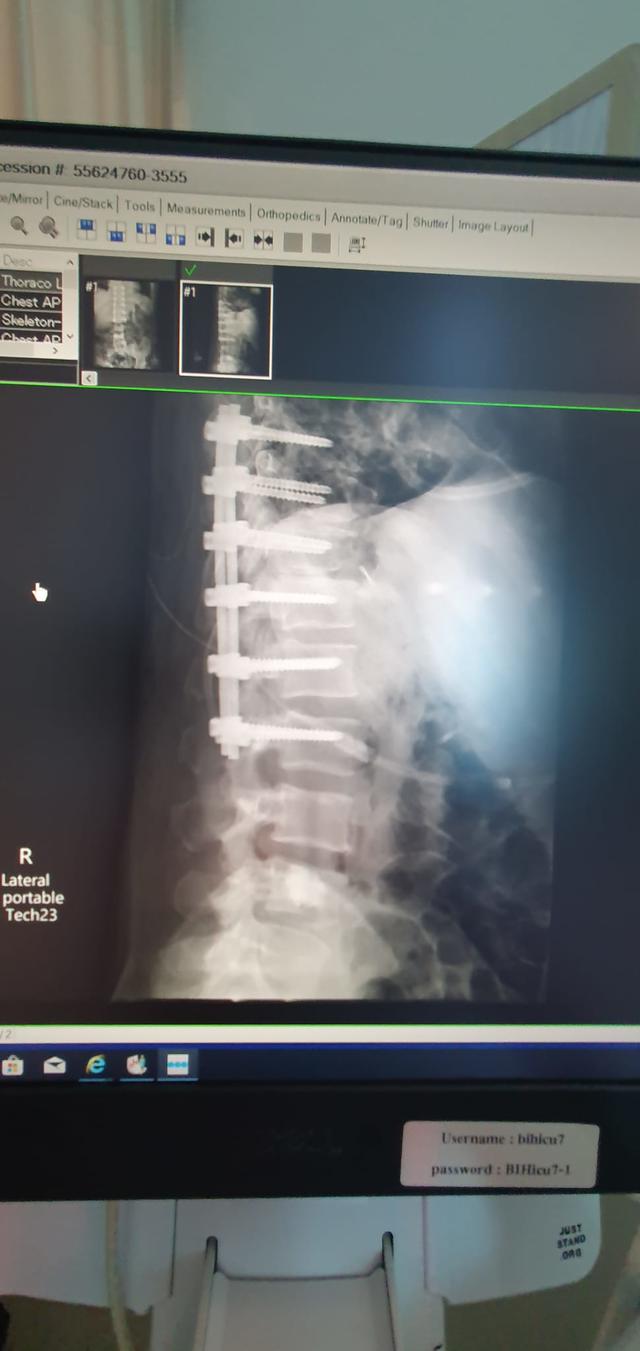

• Surgery

17 July 2023

Main image

Rod and pins to hold spine together